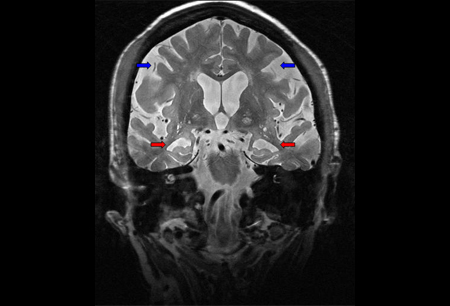

RNM cranioencefálica: mostra atrofia cortical difusa, com atrofia hipocampal predominante (setas vermelhas), em paciente com demência de Alzheimer. Atrofia parietal e envolvimento neocortical evidentes na doença mais avançada (setas azuis)

Do acervo pessoal do Dr. Geschwind, MD, PhD; usado com permissão